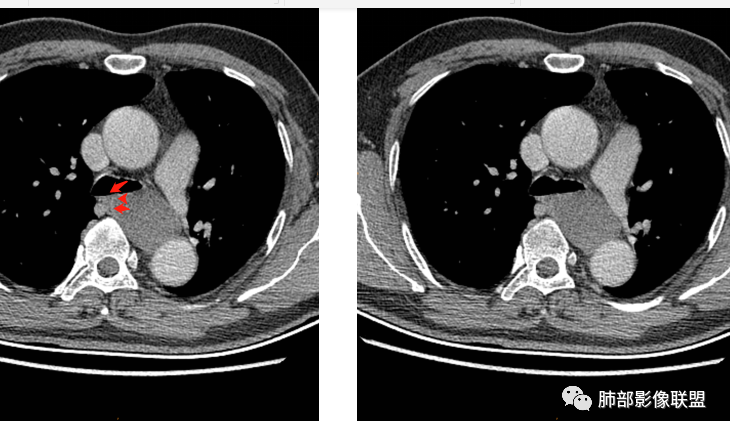

男性,43岁,体检发现后纵隔占位,边缘光整,CT示密度均匀,周围组织受压移位,无钙化囊变及脂肪组织,增强未见明显强化。MRI:T1示肿块信号较肌肉高,T2不均匀高信号。考虑为良性病变,第一是神经节细胞瘤,其次是支气管源性囊肿。

中年男性,无症状,后纵隔肿块,长径大矢状位于横径,质地偏软,塑形,等t1稍长t2,比较均质,增强轻微强化,与脊柱,主动脉,食管脂肪间隙存在,部分层面与脊柱相贴,骨质无改变,周围无肿大淋巴结,考虑神经源性肿瘤,节细胞神经瘤可能大,鉴别心包斜窦,淋巴瘤,淋巴管囊肿。

后纵隔囊性占位,密度均匀,与左主支气管分界不清,略受压,增强后强化不明显,核磁上看肿块局部突出,信号欠均匀,考虑良性,节细胞神经瘤可能大,支气管囊肿待排。

气管、左主支气管后方,食道左侧囊性占位,壁薄且均匀、光滑。气管及左主支气管受压凹陷、变形。

食道也受压变形、移位。

(1)圆形或椭圆形、边缘光滑的病灶,囊壁薄,囊壁可见钙化;由于病变的支气管起源性,囊壁可见属于气管壁的软骨成份.

(2)囊液密度均匀,根据性质的不同而呈不同密度,可为近似水样密度,也可为较高密度,因为囊壁分泌粘液,所以囊内密度一般高于其他纵隔囊肿,CT值多大于20HU甚至超过60HU;

(3)若囊肿内密度较高时与实性肿块鉴别较为困难,增强扫描囊液无强化为鉴别要点;但是囊壁因为含有平滑肌成份,所以可能环形强化;如果病灶合并感染,病灶壁也会明显强化。